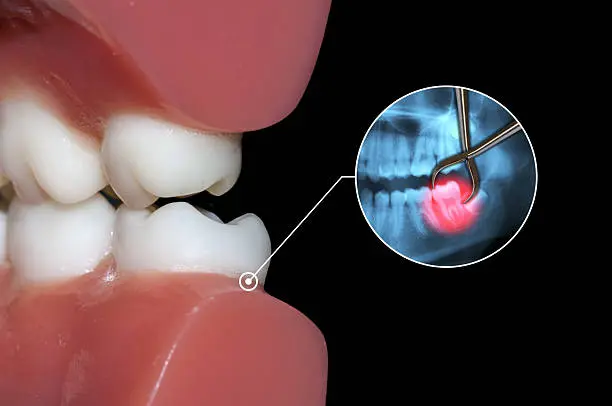

ทำไมต้องผ่าฟันคุด

เพื่อป้องกันปัญหาเกี่ยวกับช่องปาก ฟันผุ เหงื่อกอักเสบ ฟันซ้อมเก ไม่ควรปล่อยให้ฟันคุดฝั่งอยู่ในขากรรไกร เพราะอาจะทำให้แนวฟันอื่นเสียหายจากการดันตัวของฟันคุด และที่สำคัญคือส่งผลให้มีอาการปวดฟันคุดรุนแรง